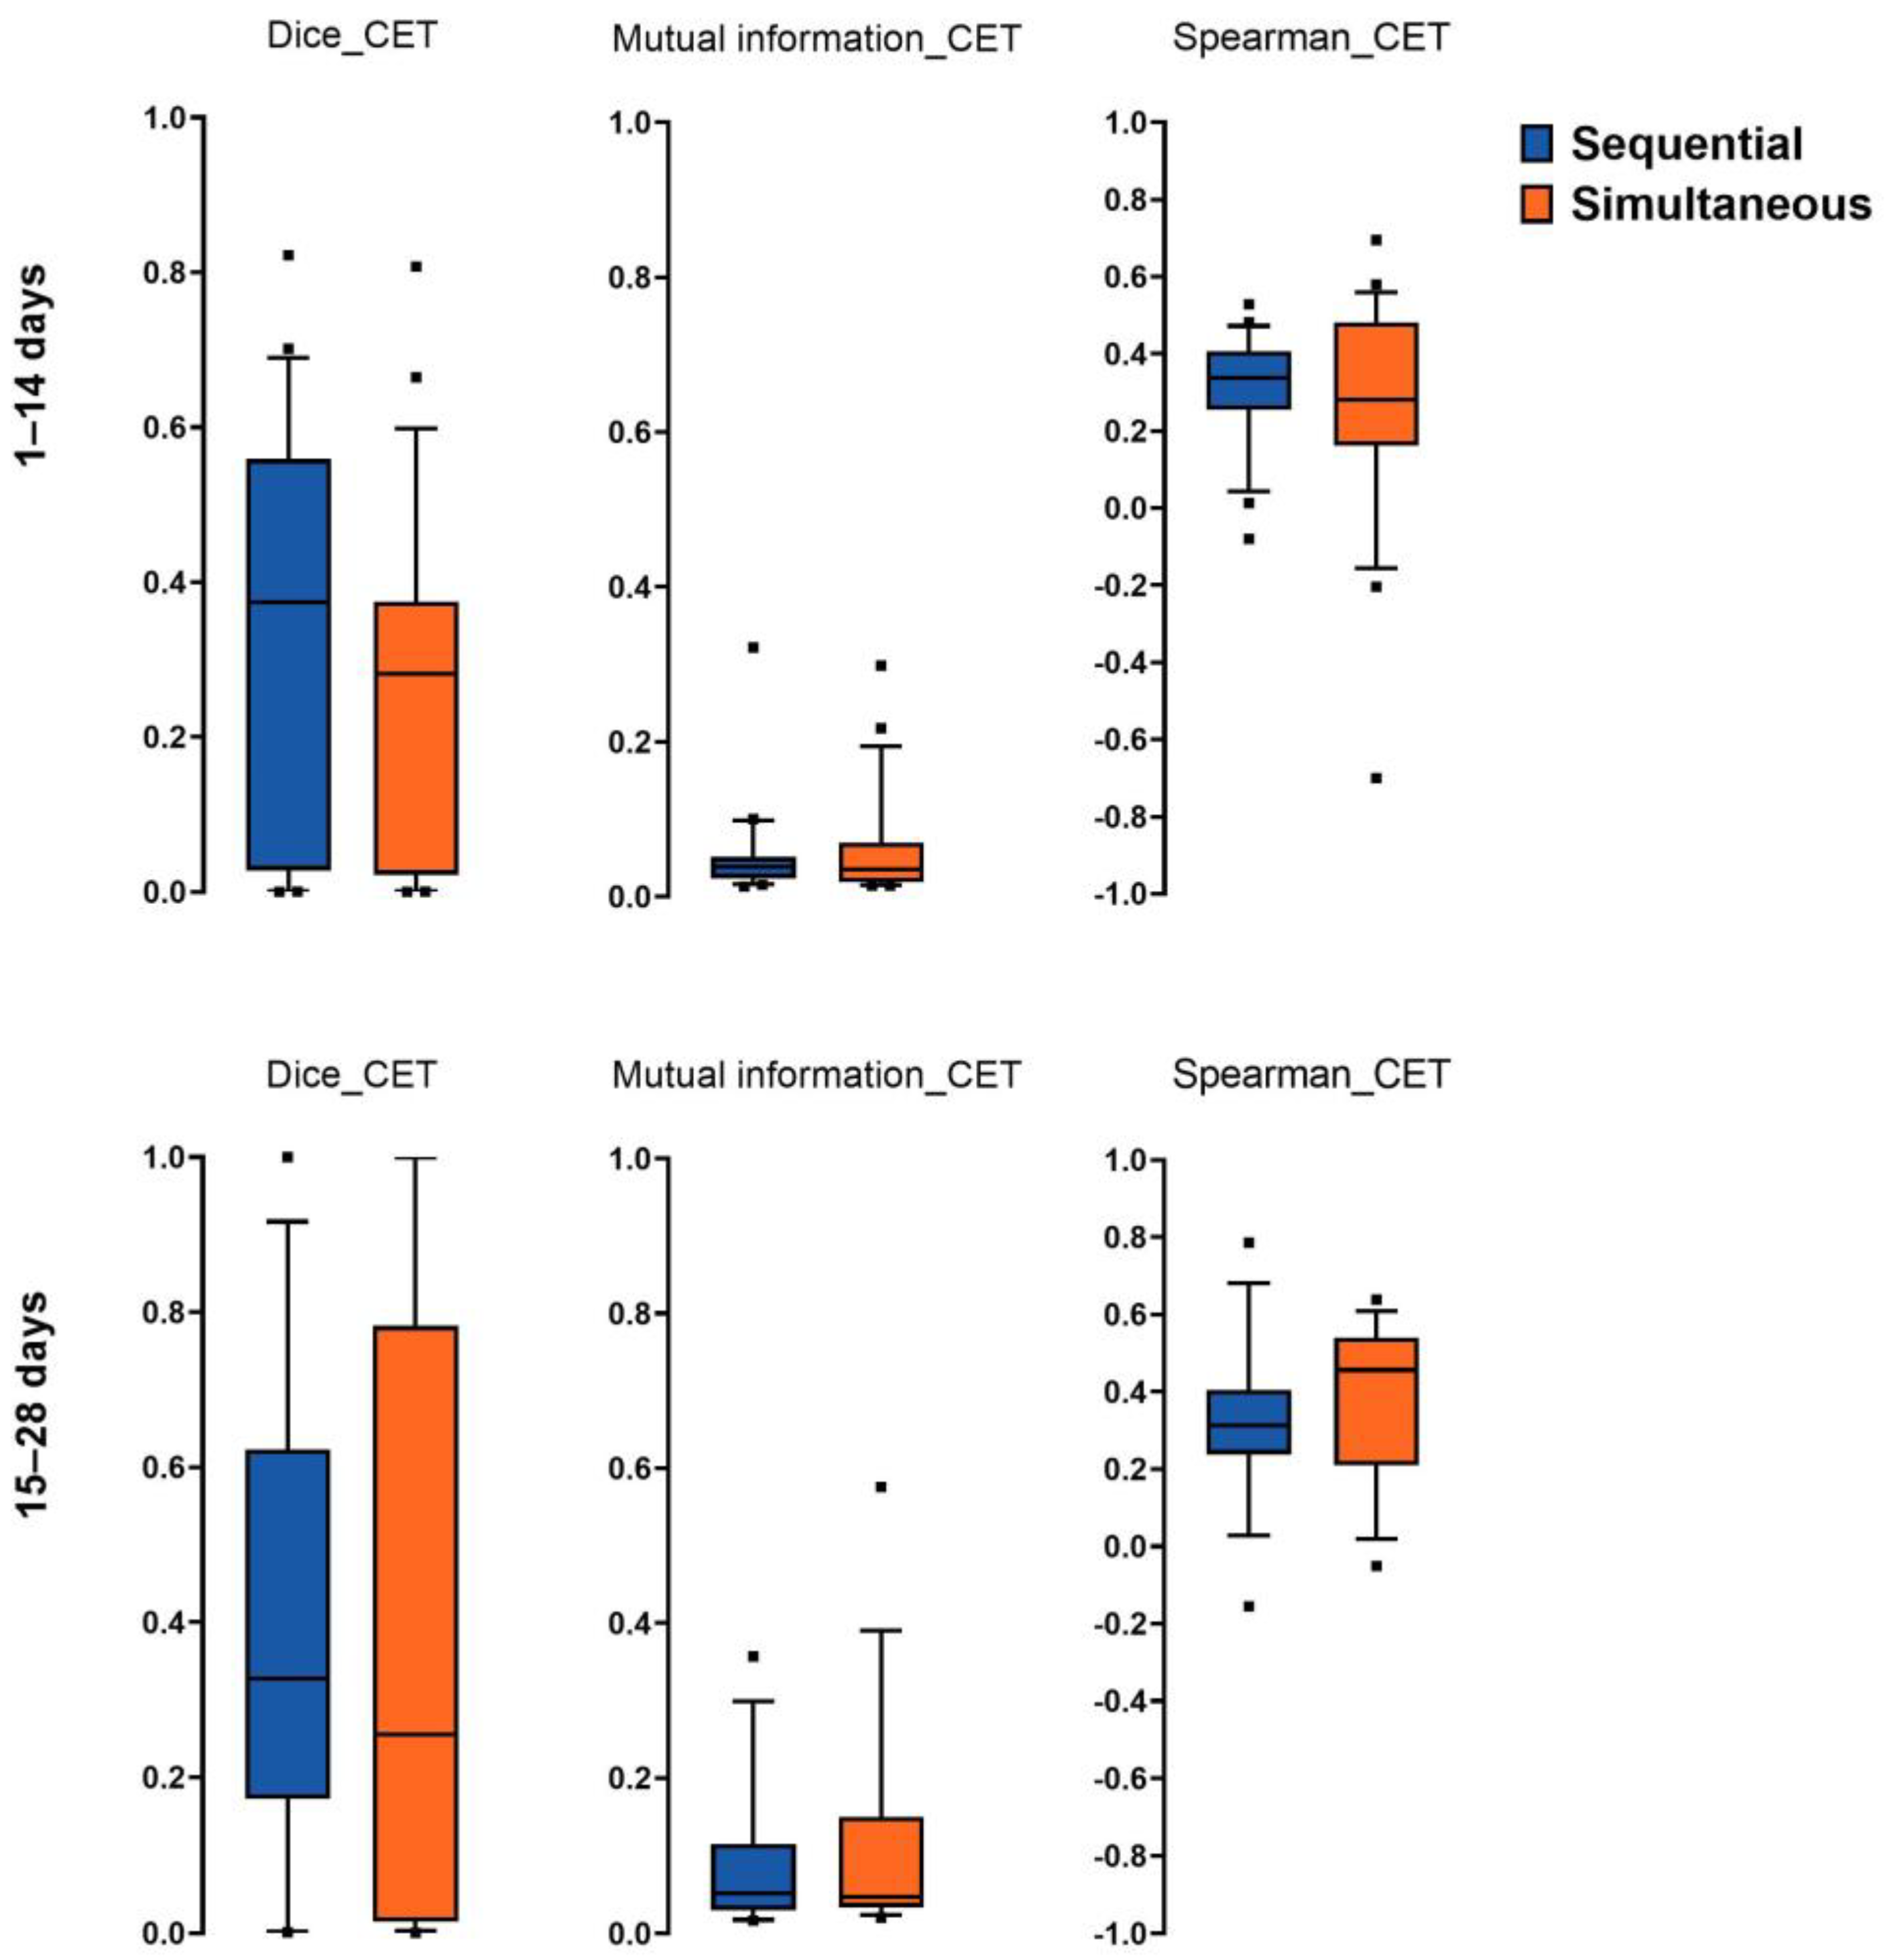

3.2. Spatial Overlap, Mutual Information, and Spearman Correlation of Imaging Hotspots